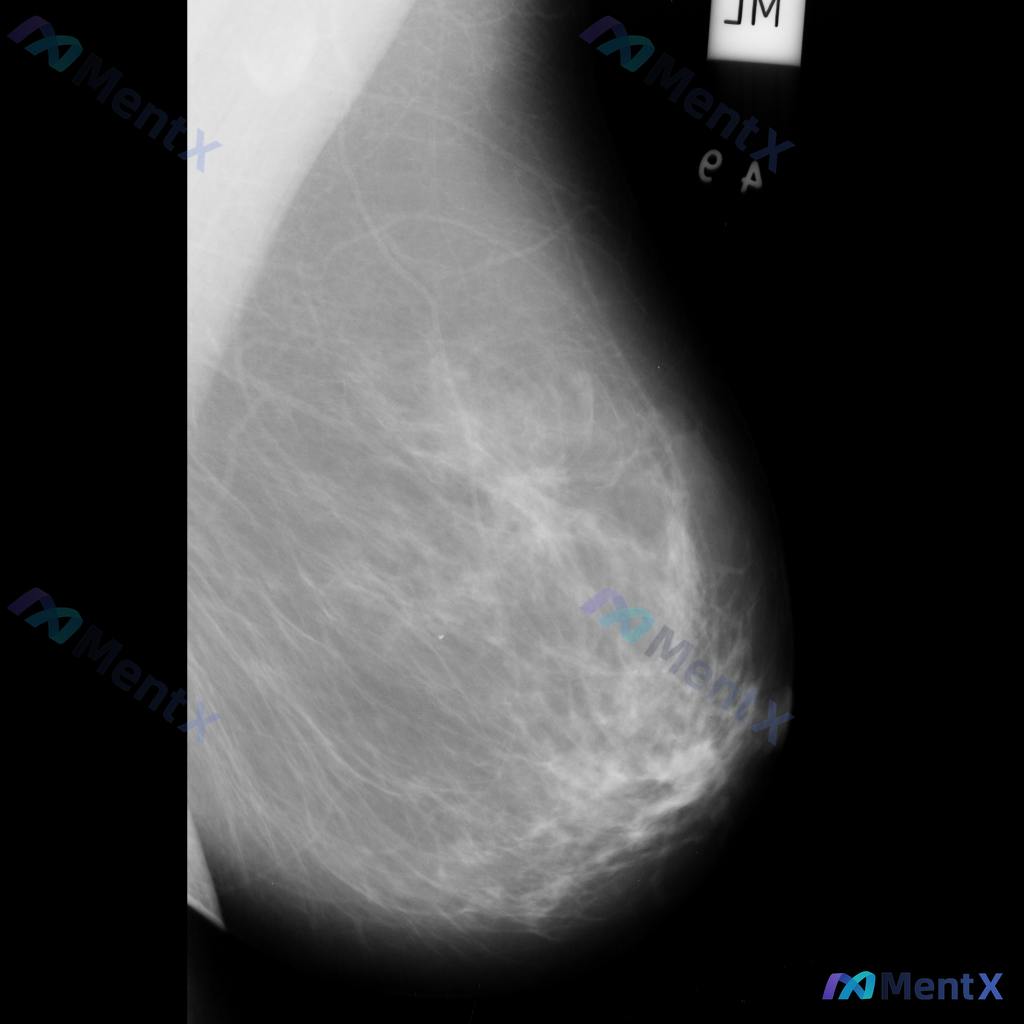

这张乳腺钼靶影像的异常表现,最适合用什么术语描述?

整理到一张乳腺钼靶影像资料,大家一起讨论下。 影像表现大概是这样: - 异常区域位于乳腺下象限偏外侧 - 可见一局限性致密影,形态大致呈卵圆形或不规则形 - 边缘部分清晰,局部可能模糊或有细微毛刺样改变 - 致密影密度高于周围脂肪组织,与纤维腺体组织密度相似或略高 - 周围乳腺小梁结构似有轻微的牵拉...